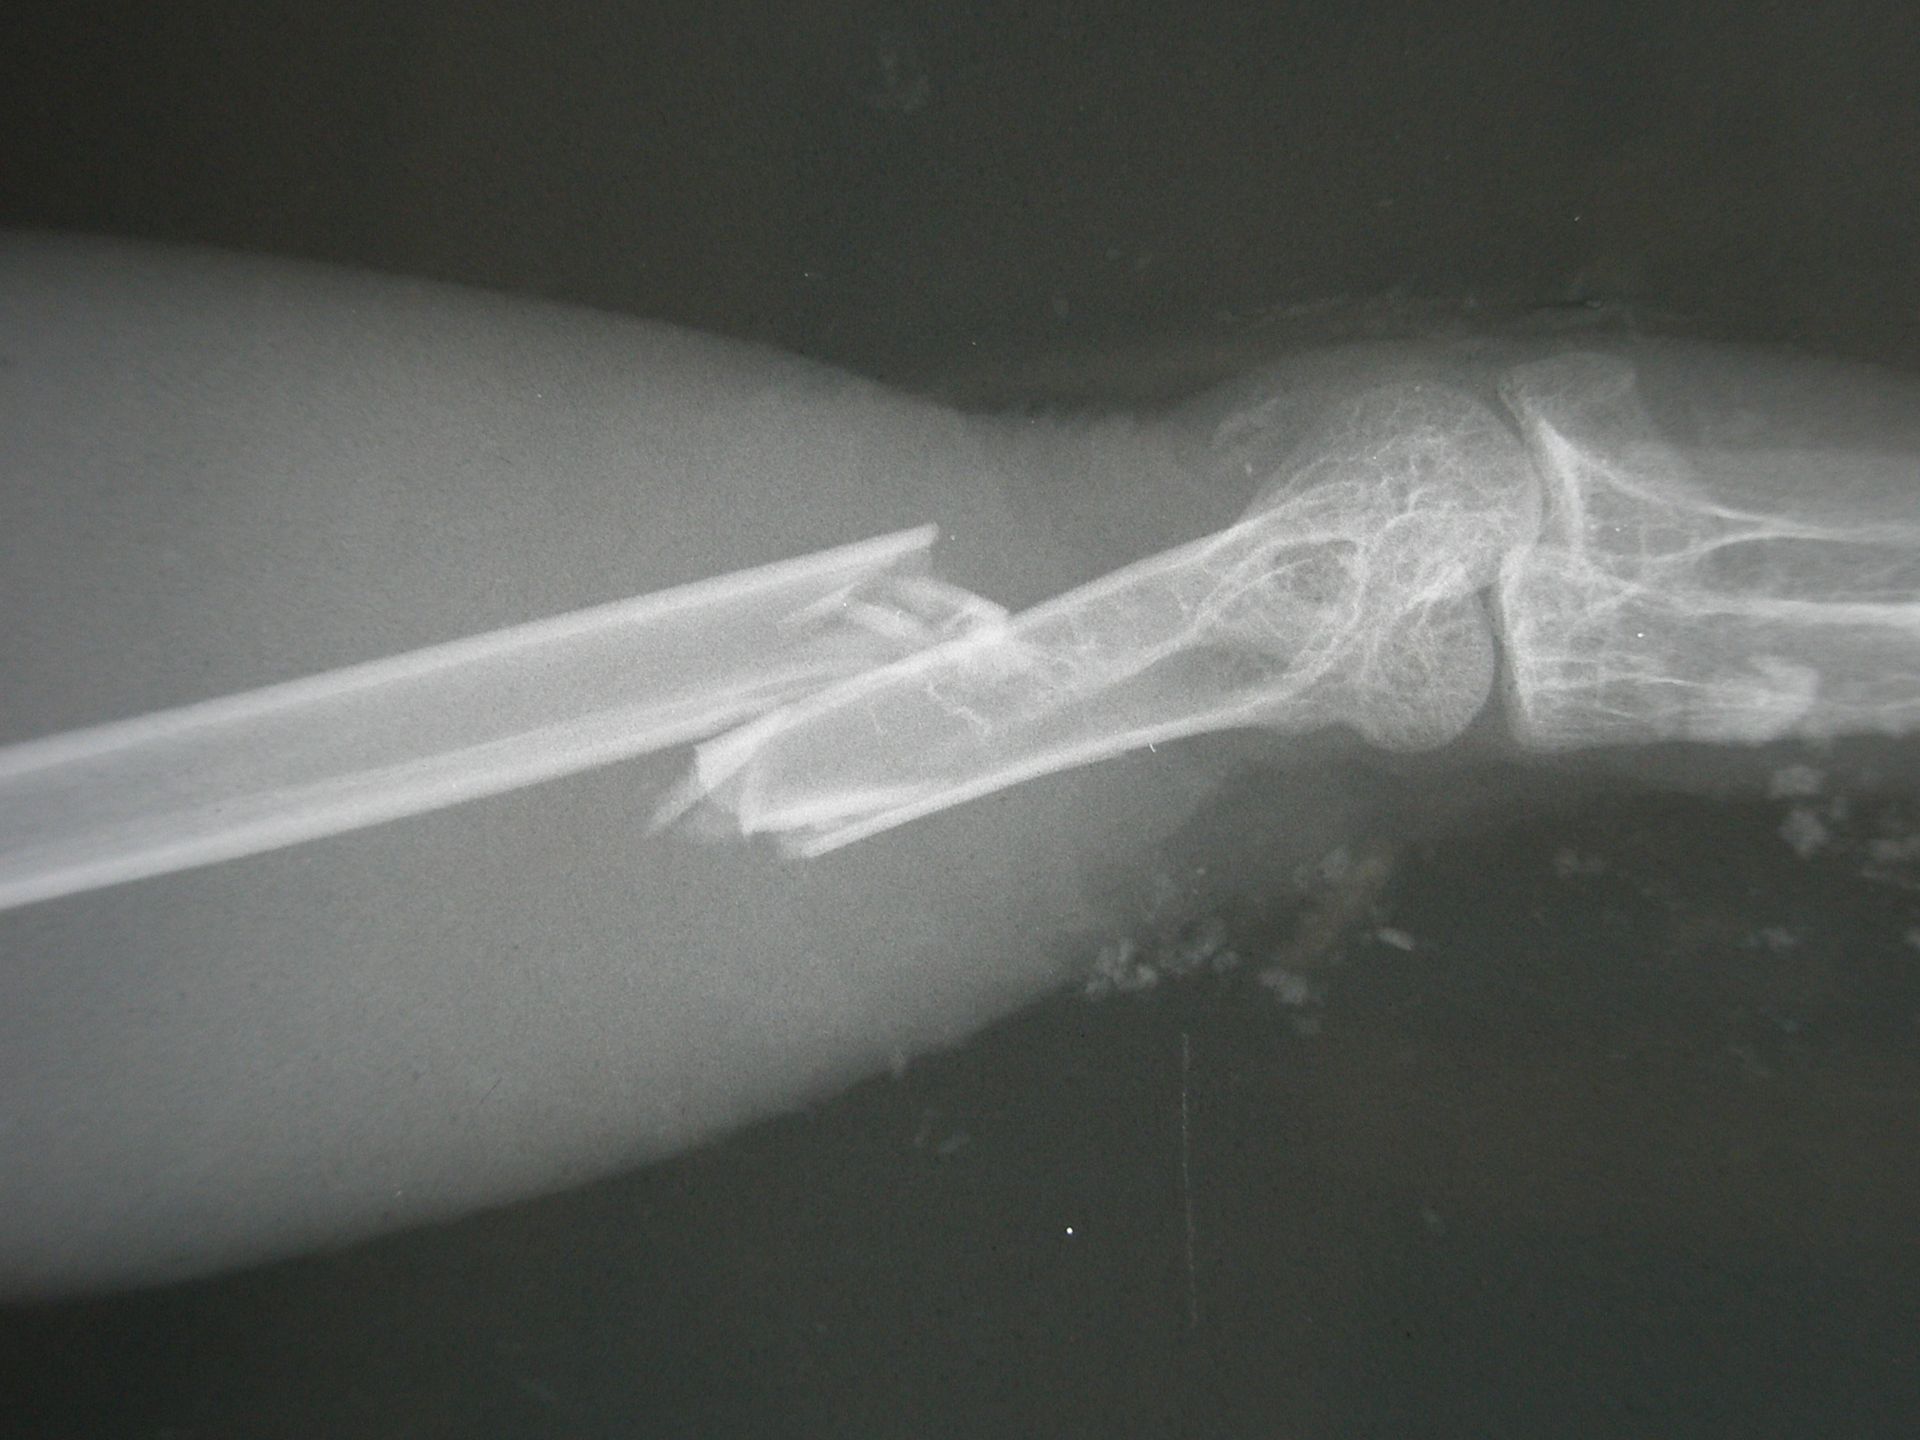

Les fractures sont très fréquentes chez les oiseaux du fait de la fragilité des os qui sont souvent pneumatiques et donc rempli d'air. Les os les plus souvent affectés sont le tibiotarse (l'équivalent du tibia des mammifères) ou l'humerus.

La plupart du temps, les fractures doivent être stabilisées et opérée chirurgicalement pour conserver la fonctionalité du membre. Chez les oiseaux plus petits des systèmes d'attelle peuvent être considérée.

La gestion de la fracture inclue en priorité une gestion de la douleur et une hospitalisation pour du repos et éviter une aggravation de la fracture. Il est important également de faire une évaluation radiographique et vérifier l'absence de maladie sous jacente tel qu'un manque de calcium.